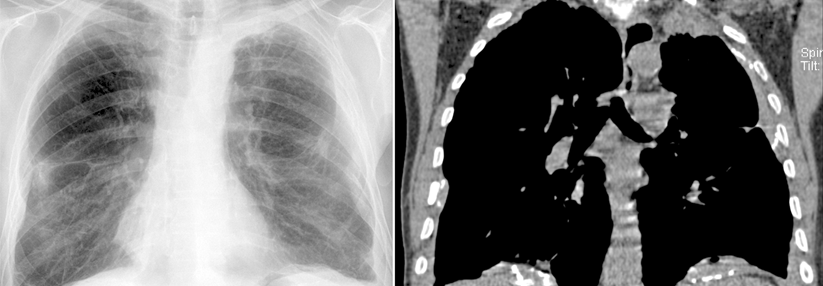

Das Röntgenbild (links) und das CT-Bild (rechts) sollten einen Verdacht auslösen. Die Pleura ist verdickt und es gibt einen Erguss. Das Röntgenbild (links) und das CT-Bild (rechts) sollten einen Verdacht auslösen. Die Pleura ist verdickt und es gibt einen Erguss. © wikipedia/Hellerhoff (CC 3.0)

Bei klinischem oder radiologischem Verdacht ist der erste dia­gnostische Schritt die Thorax-CT. Sie zeigt diffuse oder noduläre Pleura­verdickungen, disseminierte Rundherde und abgekapselte Ergüsse. Diese Befunde sind zwar typisch für das MPM, aber nicht pathognomonisch. Sichern lässt sich die Diagnose nur histologisch, z.B. mit einer Videothorakoskopie. Die Immunhistochemie ermöglicht den Nachweis von tumorspezifischen Markern und erlaubt die Einteilung in vier Subtypen: epitheloid, sarkomatoid, biphasisch-epitheloid und biphasisch-sarkomatoid.

Mesotheliom der Pleura links in der Computertomographie: Mantelförmige Verdickung der Pleura mit Pleuraerguss. Mesotheliom der Pleura links in der Computertomographie: Mantelförmige Verdickung der Pleura mit Pleuraerguss. © wikipedia/Hellerhoff (CC 3.0)